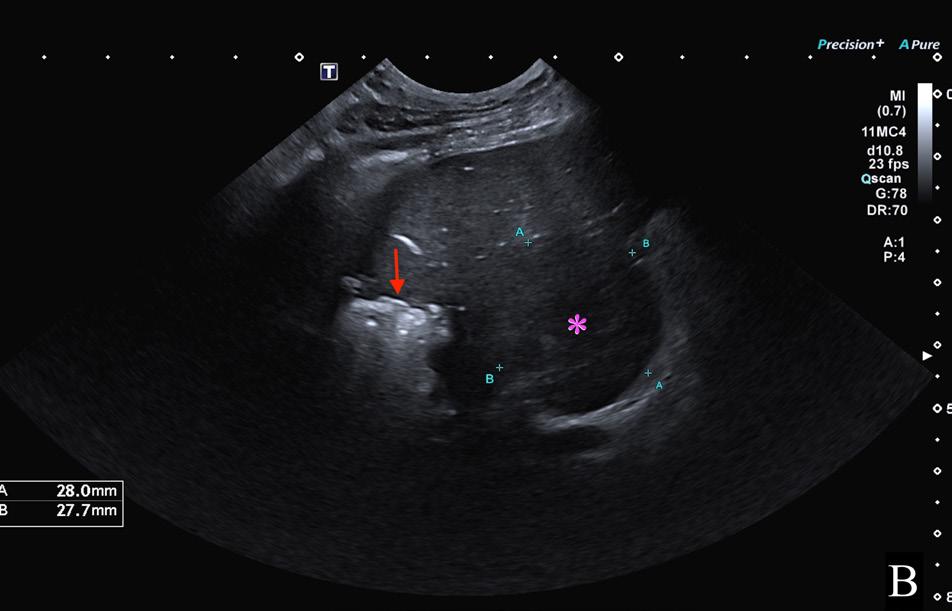

El examen neurológico evidenció paraparesia no ambulatoria y retraso en las reacciones posturales de ambas extremidades posteriores, más marcado en la extremidad posterior izquierda (EPI) (Fig.1). Los reflejos patelar, flexor y perineal estaban disminuidos y la nocicepción, intacta. El paciente presentaba parálisis de la cola con pérdida de nocicepción. La exploración de los pares craneales y las extremidades anteriores fue normal. No se detectó dolor espinal durante la evaluación. El examen neurológico fue compatible con una lesión localizada entre los segmentos espinales L4-S3.

Las pruebas diagnósticas realizadas incluyeron análisis de sangre, radiografía laterolateral de tórax y ecografía abdominal, sin resultar en alteraciones significativas. La serología frente al virus de la leucemia e inmunodeficiencia felina resultó positiva para esta última. En el estudio de resonancia magnética (RM; Fig. 2) de la región toracolumbosacra (Toshiba Vantage Elan 1.5 T: Adquisición de planos transversal, sagital y coronal ponderados en T1 pre y post-contraste intravenoso con gadolinio, así como planos ponderados en T2 y STIR) se cuentan 6 vértebras lumbares, lo cual es compatible con anatomía de transición en la región lumbar, como hallazgo incidental. En el lado izquierdo del canal vertebral, desde el tercio craneal de la vértebra L5 hasta el tercio caudal de la vértebra L6 se encuentra una lesión con aspecto alargado y de base ancha, con márgenes mal definidos e irregulares, distribución posiblemente extradural y/o intradural/extramedular, causando compresión severa de la médula espinal, que aparece desplazada hacia el lado derecho. En cuanto al patrón de intensidad de la señal, este fue hiperintenso de forma homogénea en las secuencias ponderadas en T2 e isointenso en las secuencias ponderadas en T1, con un realce homogéneo y focal en la región media de la vértebra L6. La lesión se extiende parcialmente en el foramen intervertebral izquierdo entre las vértebras L5 y L6 y se aprecia siringomielia leve, que puede ser un proceso secundario a la compresión de la médula espinal por parte de la lesión, más caudalmente a nivel lumbar.

Figura 2. Imágenes de RM postcontraste en las que se identifica una lesión de forma alargada y ancha en su base, con distribución posiblemente extradural y/o intradural/extramedular a nivel de la vértebra L6 (flechas rojas). (A) Secuencia dorsal en STIR. (B) Secuencia transversal en T2. Nótese la compresión severa a la que es sometida la médula espinal (flecha verde). (C) Secuencia transversal en T1 precontraste. (D) Secuencia transversal en T1 postcontraste. M: masa; SC: médula espinal; R: derecha; L: izquierda.